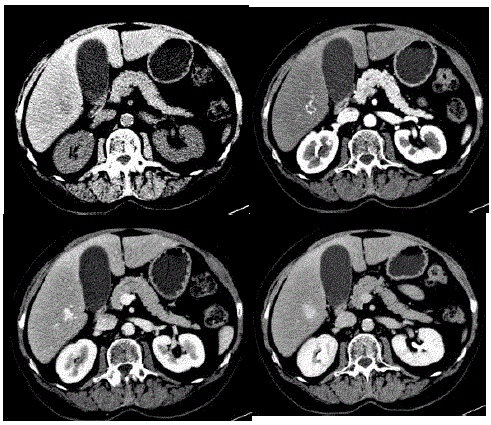

Mulher de 33 anos, em uso de anticoncepcional oral há 18 anos, realiza tomografia em investigação de dor abdominal, que evidenciou o nódulo hepático mostrado na imagem a seguir:

Qual é a melhor conduta?